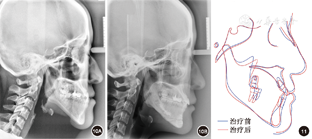

患者女性,23岁。主诉:"地包天",面部不对称,要求改善面型。7年前曾于外院行正畸治疗1.5年,后随生长复发;否认家族史。

患者正面观不对称,颏部右偏4.0 mm,面下1/3过长。侧面凹面型,上颌轻度后缩,下颌前突。口内检查:

残根,右侧磨牙近中关系,左侧完全近中关系;前牙浅覆

、浅覆盖;上牙列无拥挤,下牙列拥挤2.0 mm。上中线正,下中线右偏5.4 mm。

过小牙,

烤瓷联冠,

颊向倾斜,

舌向倾斜。X线检查示上颌后缩,下颌前突伴偏斜。头影测量显示上颌突度的SNA角73.82°,下颌突度的SNB角76.64°,上下颌相对位置的ANB角-2.82°,L1/MP角(下中切牙与下颌平面所成角度)64.95°。

安氏Ⅲ类错

畸形,毛氏Ⅱ1;骨性Ⅲ类,上颌后缩下颌前突伴偏斜。